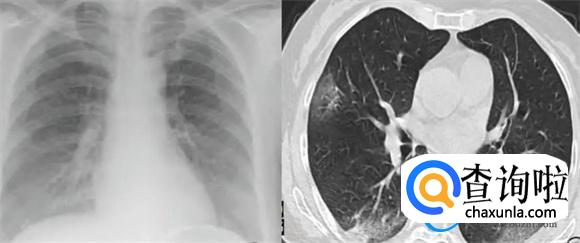

白肺主要是指肺部已经出现了重度的感染,肺泡当中有炎症或者是感染,肺泡已经生出了渗出液体和炎性的细胞。在通过CT或者是X光线的时候,所呈现出的白色区域,白色区域一般达到70%~80%,在临床上才会称之为白肺。